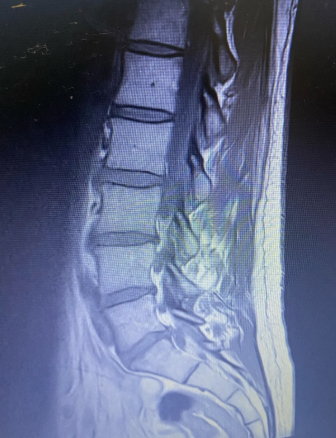

MR ledvenega dela hrbtenice. Na sliki je vidna križnica, ledvena vretenca in T12. Opazite izrazit nagib križnice naprej in poravnano ledveno krivino od L3 navzgor.

Na sliki sta vidna križnica in vsa ledvena vretenca do T12. Ledvena vretenca bi morala pri zdravi hrbtenici tvori lordozo — rahlo konkavno krivino, ki omogoča amortizacijo in učinkovit prenos sil od spodaj navzgor in nazaj.

Kar sem videl na sliki: križnica je v izrazitem nagibu naprej. S tem nagibom izpodriva L5 nekoliko nazaj. Ker L5 ni v idealnem položaju, se disk potisne v hrbtenjačo. Hkrati ledvena vretenca od L3 navzgor kažejo poravnano krivino — ne lordoze.

Ledvena krivina ni ohranjena. Ima spremenjen obliko: križnica je napram ledvenim vretencem bolj nagnjena naprej kot bi morala biti, kar otežuje prenos sil in izpodriva disk. Ortoped je le opisal videz, ne pa dejanskega stanja.

Ohranjena krivina pomeni enakomerno razporejen lok. Tukaj pa je bila spodnja tretjina hrbtenice v skrajnem anteriornem položaju, zgornji del pa poravnan. Skupni videz je bil "nekako v redu", mehanično pa je bila razporeditev sil neoptimalna.